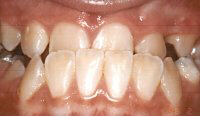

![]() |

Trước chỉnh hình |